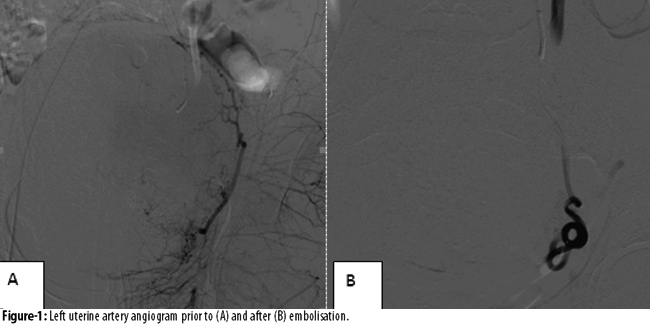

After placing a 5Fr vascular access sheath, a 4Fr C2 catheter was advanced over hydrophilic guide wire into the left internal iliac artery and diagnostic angiography was performed. The 4Fr catheter was used for selective catheterisation of the uterine artery and embolisation (Figure 1a and 1b).

In case of severe tortuosity and difficult catheterisation, a micro-catheter was used to avoid vasospasm. Finally, 500-700µm and 300-500µm polyvinyl alcohol (PVA) particles were slowly infused into the artery and "near-stasis of flow" in uterine arteries was considered the end point of the procedure.